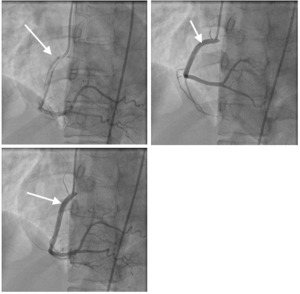

The patient was taken to the catheterization lab by the cardiology team. The result of the procedure was consistent with spontaneous dissection of the right coronary artery. (Figure 2) There was no intervention performed. The cardiothoracic surgeon who decided that there is no need for surgical intervention also evaluated the patient. She was medically managed and discharged home with aspirin, atorvastatin, metoprolol, and Plavix. Her hospital course was uncomplicated and she was discharged home in stable condition.